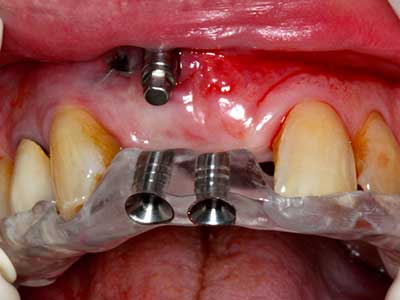

Il tessuto osseo non è semplicemente una struttura minerale, ma contiene anche una percentuale significativa di fibre di collagene. Ciò significa che non possiede solo una buona forza di compressione, ma anche un certo livello di flessibilità che è possibile sfruttare durante l'esecuzione degli accrescimenti di osso. Nella procedura di espansione classica con incisione ossea, la cresta alveolare atrofizzata viene incisa longitudinalmente ed espansa con cautela dopo aver raggiunto una profondità di osteotomia adeguata (figg. 13-16), idealmente senza una sostanziale rimozione del periostio (Brugnami, Caiazzo et al. 2014, Stricker, Fleiner et al. 2014). I sistemi a piastra e vite con distanza di espansione incrementale si sono dimostrati efficaci nella separazione delle due lamelle ossee restando al di sotto della soglia di frattura. In generale, sono richieste larghezze dell'osso residuo di almeno 3-4 mm (Chiapasco, Zaniboni et al. 2006) per garantire un'adeguata flessibilità e una copertura sufficiente dell'osso per gli impianti futuri. Se necessario, un'osteotomia di rilascio verticale su uno o più lati può migliorare la flessibilità. Una combinazione con ulteriori tecniche di accrescimento, in particolare dal lato buccale, è stata descritta come un'alternativa alla tecnica classica.

La procedura di incisione è particolarmente atraumatica e non comporta una perdita significativa di dimensione durante l'utilizzo delle seghe piezoelettriche, così come non si notano differenze rilevanti tra impianti in mandibole incise e impianti in una cresta alveolare senza deficit osseo (Chiapasco, Zaniboni et al. 2006, Danza, Guidi et al. 2009). Una sufficiente irrigazione continua è essenziale, tuttavia, in particolare con incisione profonda e localmente ristretta, per prevenire la sollecitazione termica nelle regioni apicali dell'osteotomia.